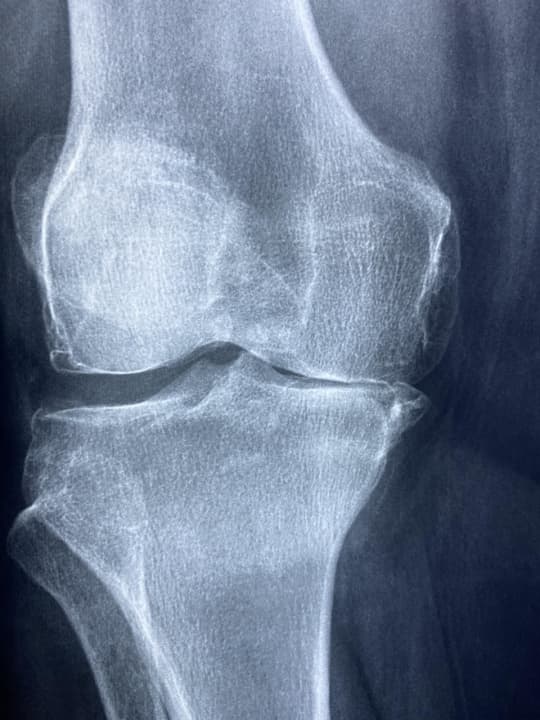

Komplex térdsérülés preoperatív fizioterápiás menedzsmentje: ACL szakadás, laterális meniscus és MCL sérülés konzervatív kezelése mellett

A komplex térdsérülések – különösen az elülső keresztszalag (ACL) szakadás, laterális meniscus sérülés és medialis collateralis szalag (MCL) szakadás együttes előfordulása – multidiszciplináris kezelést és jól strukturált preoperatív fizioterápiás protokollt igényel. A sikeres ACL-rekonstrukció egyik kulcsa a műtét előtti állapot optimalizálása, különösen, ha a társuló sérüléseket konzervatívan...

Ligamentum collaterale mediale (MCL) részleges szakadásának (Grade II) kezelési protokollja

A ligamentum collaterale mediale (MCL) grade II-es, azaz részleges szakadása gyakori térdsérülés, különösen sportolók körében. A szakirodalmi adatok és nemzetközi kezelési irányelvek alapján az esetek túlnyomó többsége konzervatív, nem műtéti terápiával eredményesen rehabilitálható. A kezelési protokoll három fő szakaszra tagolható: az akut fázis (1–2. hét) célja a fájdalom és gyulladás csökken...